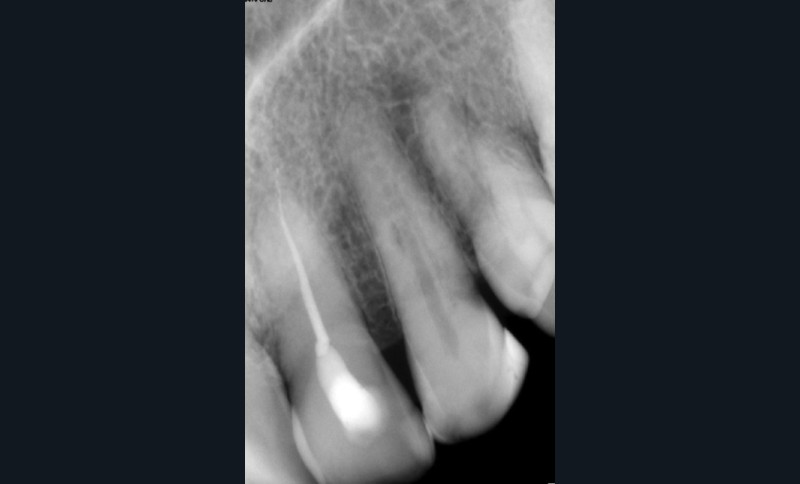

L’utilisation du scanner, et maintenant du CBCT, bouleverse l’idée très radiographique que nous avions du système canalaire.

En effet, la culture endodontique, fondée sur les critères radiographiques, a fait oublier les études de Hess et Zurcher (1925) qui mettent en évidence la complexité du système endo-canalaire [1]. Ce système présente une cavité principale (par exemple, le canal principal) ainsi que des canaux accessoires/latéraux. 25 % de ces microcanaux peuvent être interconnectés les uns aux autres, avec une densité plus importante de ramifications dans la région apicale du canal principal [2].

Rebondissant sur l’imagerie 3D et la mise en évidence des anatomies canalaires complexes, Peters, en 2001, décrit l’insuffisance instrumentale dans le traitement endodontique, et montre que 35 % des surfaces sont intactes après préparation canalaire correctement menée [18].

Endal, en 2011, montrait également, en utilisant le micro CT Scanner, l’insuffisance de nettoyage des isthmes inter-canalaires à nos techniques conventionnelles [19]. L’utilisation du laser Er:YAG devenait alors incontournable dans le nettoyage de ces isthmes et des zones non instrumentées (fig. 2 et 3).